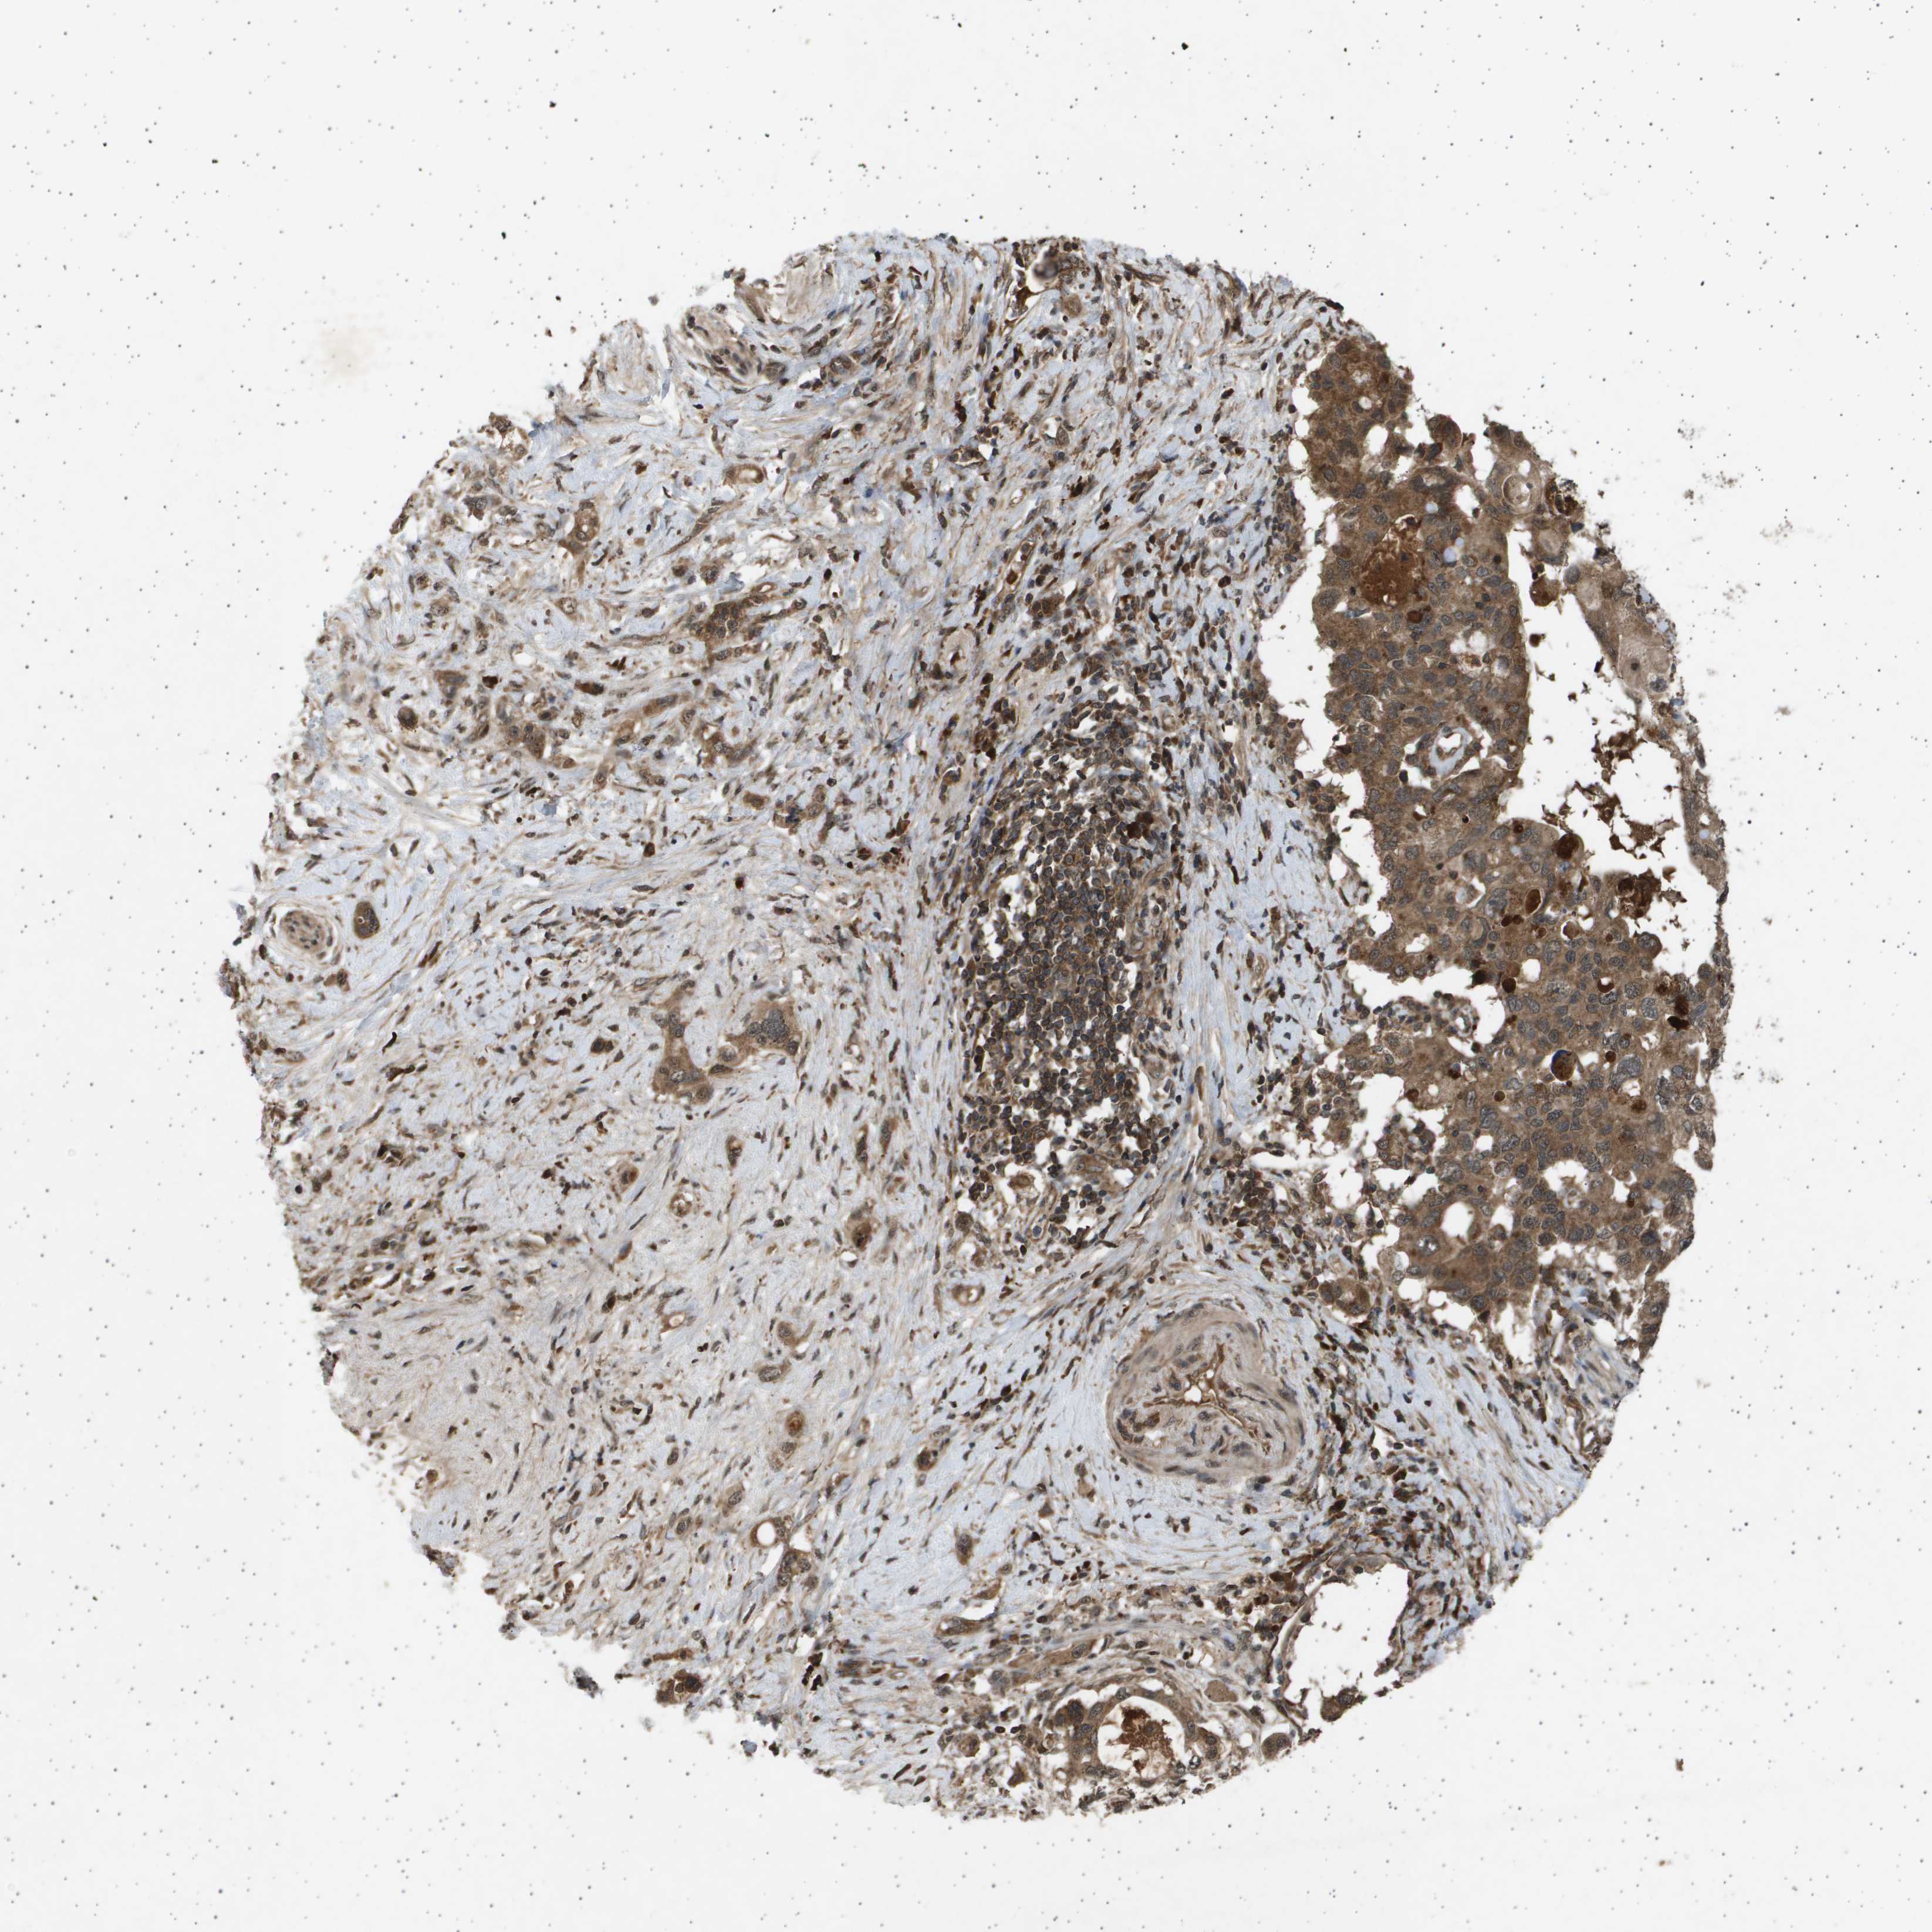

PANCREATIC CANCER - Protein expressioni

A mouse-over function shows sample information and annotation data. Click on an image to view it in a full screen mode. Samples can be filtered based on level of antibody staining by selecting one or several of the following categories: high, medium, low and not detected. The assay and annotation is described here.

Note that samples used for immunohistochemistry by the Human Protein Atlas do not correspond to samples in the TCGA dataset.

Antibody stainingi

Antibody staining in the annotated cell types in the current human tissue is reported as not detected, low, medium, or high, based on conventional immunohistochemistry profiling in selected tissues. This score is based on the combination of the staining intensity and fraction of stained cells.

Each image is clickable and will lead to virtual microscopy that enables deeper exploration of all samples and also displays staining intensity scores, fraction scores and subcellular localization as well as patient and tissue information for each sample.

Antibody HPA017869

Staining

High

Medium

Low

Not detected

Intensity

Strong

Moderate

Weak

Negative

Quantity

>75%

75%-25%

<25%

None

Location

Nuclear

Cytoplasmic/membranous

Cytoplasmic/membranous,nuclear

Adenocarcinoma, NOS